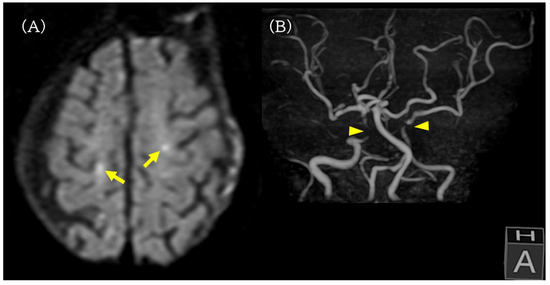

On POD 2, oxygen was discontinued and his SpO2 remained in the range of 95–98% on room air. He was able to converse and eat during the day. During sleep at night, transient desaturation into the 80% range was observed, and low-flow oxygen at 0.5 L/min was restarted, but other vital signs remained stable with systolic blood pressure in the range of 120–130 mmHg and a heart rate in the range of 80–100/min. Brain magnetic resonance imaging (MRI) performed on POD 2 revealed multiple small acute cortical infarcts in both cerebral hemispheres, and magnetic resonance angiography (MRA) demonstrated poor visualization of the bilateral internal carotid artery (ICA) siphon segments and a severe stenosis of the left ICA, indicating advanced carotid atherosclerotic disease with reduced cerebrovascular reserve (Figure 3).

Figure 3.

Brain MRI and MRA on postoperative day 2. (A) Diffusion-weighted MRI revealing multiple small acute cortical infarcts in both cerebral hemispheres (yellow arrow). (B) MR angiography showing poor visualization of the bilateral internal carotid artery siphon segments (yellow arrowhead) and a severe stenosis of the left internal carotid artery, indicating advanced carotid atherosclerotic disease and reduced cerebrovascular reserve.